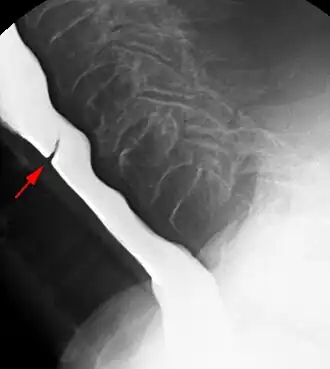

Esophageal web stenosis in barium swallow examination lateral view. -

Web with "jet-phenomenon". Arrowhead on incomplete opening of the upper esophageal sphincter. -